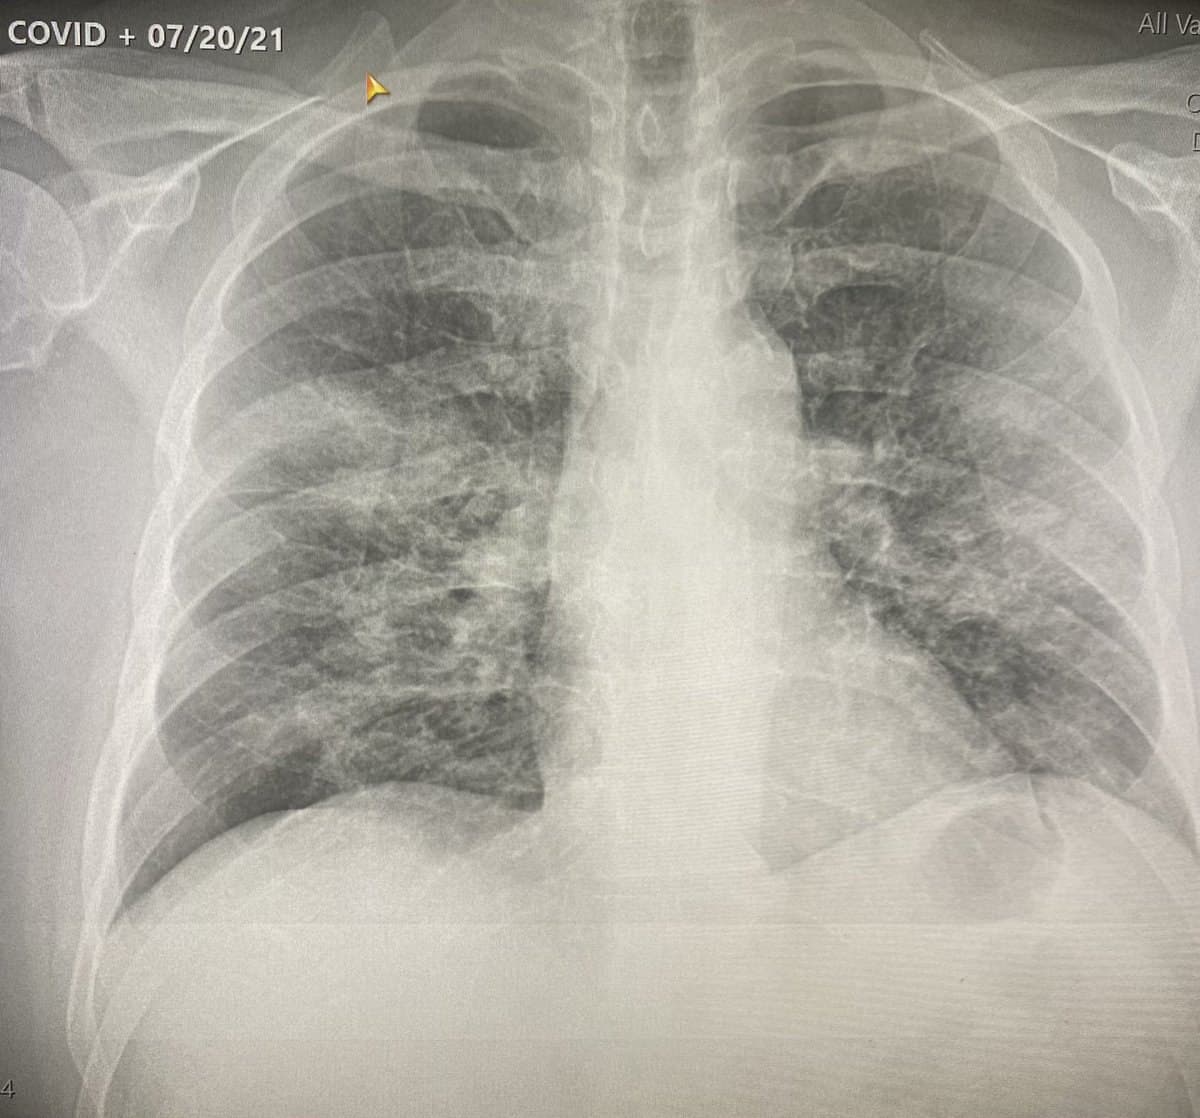

GENimpfung nützt nichts in den "USA" 7.8.2021: 2fach Pfizer GENgeimpfter wird Corona19-positiv und hat Lungenprobleme

67 male with both Pfizer vaccines presented today with COVID positive test, SOB and pulse ox 84%. This is a serious problem and people better start listening to us!

https://twitter.com/btysonmd/status/1419738805930627077?s=20

GENimpfung nützt nichts in den "USA"

7.8.2021: 2fach Pfizer GENgeimpfter wird

Corona19-positiv und hat Lungenprobleme